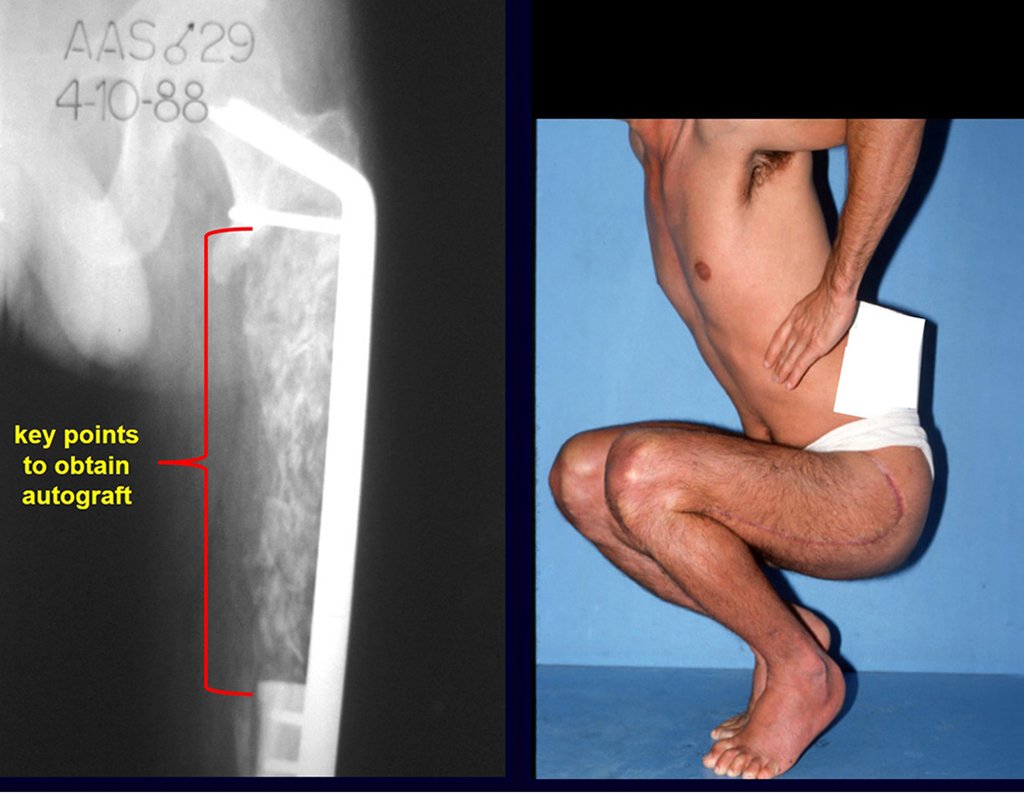

La necesidad de obtener injertos en cantidad, para viabilizar grandes reconstrucciones biológicas, nos hizo mejorar la técnica quirúrgica para obtener injertos autólogos con menor morbilidad y en cantidades significativamente mayores.

¿Es posible obtener un injerto óseo autólogo para rellenar un defecto óseo grande, de una sola placa interna de la ilíaca, como el de la figura 7? Demostremos que sí es posible, figura 8.

Los puntos clave y la técnica para obtener un buen injerto de hueso ilíaco se describen en

figuras. La incisión debe ser superficial, únicamente en la piel y tejido subcutáneo, para no dañar el nervio sensitivo cutáneo femoral lateral. Antes de proceder a la disección cauterizamos cuidadosamente los vasos subcutáneos con electrocauterio. figuras 9 y 10.